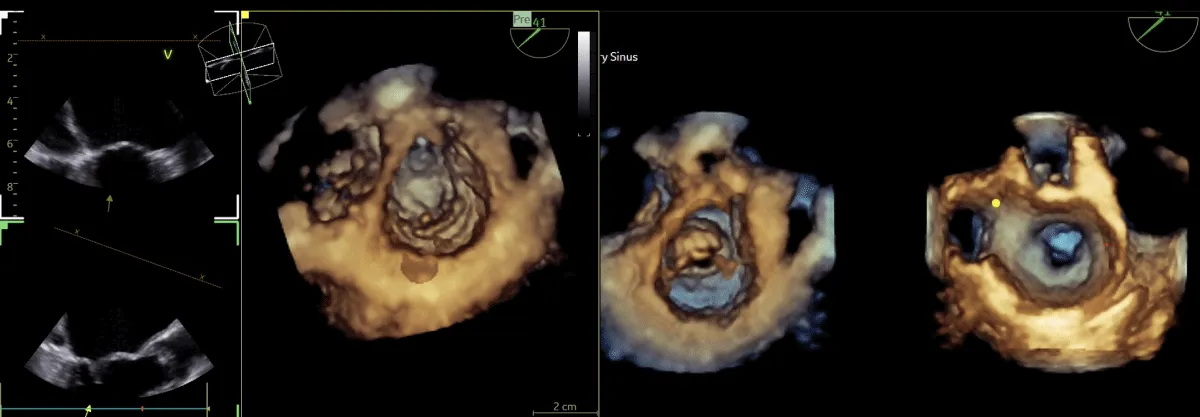

After obtaining consent, access was obtained through the right femoral vein and artery. Under 4D Transesophageal Echocardiography (4D TEE) guidance, the first transseptal puncture was performed with a broken Brough needle, and the LA wire was inserted through femoral venous access (Figure 1). Right femoral artery access was used for retrograde crossing of the aortic valve (AV) (Figure 2), and a Teflon wire was placed in the left ventricle. The aortic valve (AV) was dilated with a 14 mm ATLAS GOLD (BARD) balloon (Figure 3, Video 1).

Figure 1: A,B: 4Dimensional multiplanar transoesophageal echocardiography. A. 4D image with Left atrial wire, B. Severe mitral stenosis with mitral area of 0.5 cm2, 1C &1D. Showing multiplane of mitral valve.

Following a single dilatation, the AV gradient decreased from 82 mm Hg to 30 mm Hg without aortic regurgitation (AR). Subsequently, the mitral valve (MV) was dilated with a 26 mm Inoue balloon (Figures 4,5) (Video 2). After a single dilatation, the MV gradient was reduced from 35/21 mm Hg to 12/5 mm Hg, and the MV area increased from 0.5 cm2 to 1.6 cm2 (Figure 6)

Figure 5: 4Dimensional multiplanar transoesophageal echocardiography – Balloon dilatation of the mitral valve with Inoue balloon.

Figure 6: 4Dimensional multiplanar transoesophageal echocardiography – mitral valve after balloon dilatation.